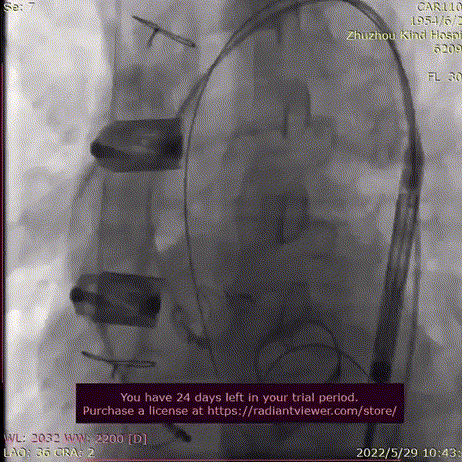

释放脱钩后瓣膜形态、位置良好,冠脉血流灌注正常,无瓣周漏。

释放脱钩

术后造影